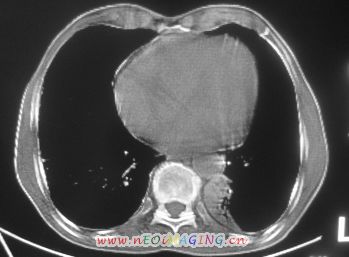

以下是引用卜一在2007-10-7 9:38:00的发言:[br]左下肺胸膜下团片影,内见含气支气管像,临近胸膜未见增厚。多考虑:1 左下肺炎症,建议消炎后复查!2 不除外肺隔离症合并感染!